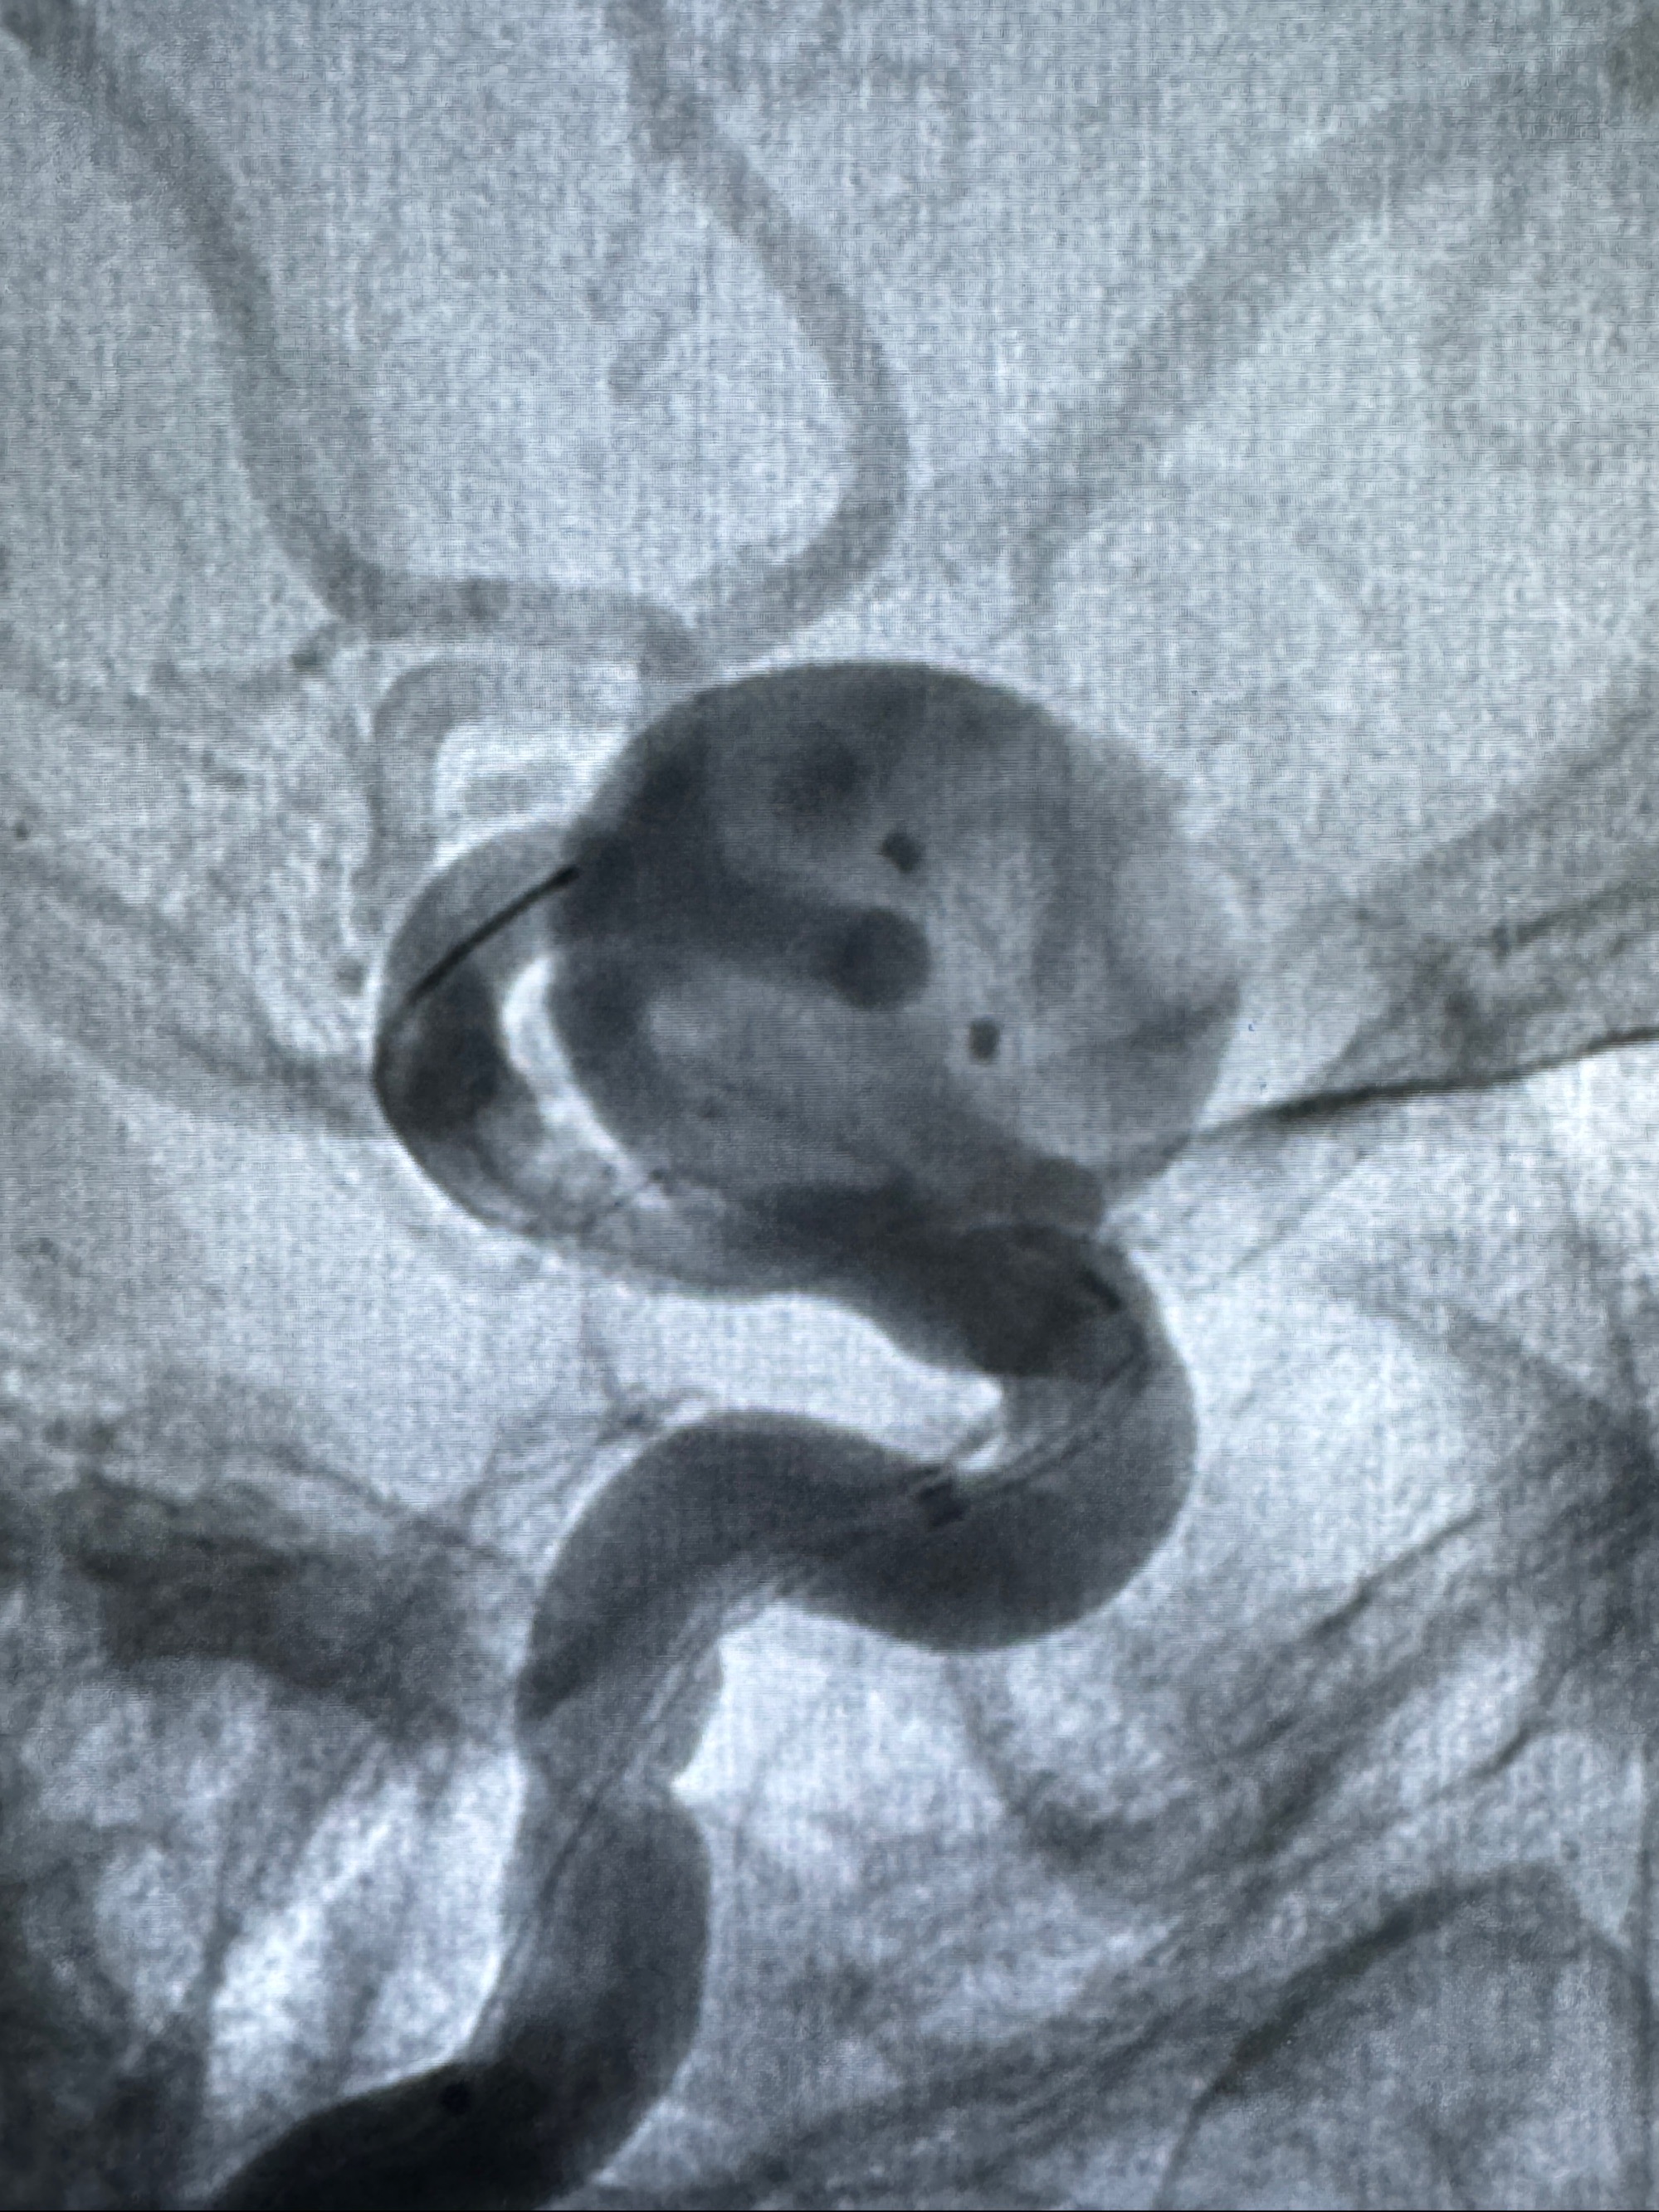

现病史:患者诉2年来反复发作性头痛,顶枕部为主,因自己考虑高血压可能,未予系统检查;患者约20日前无明显诱因下突发剧烈头晕,有天旋地转感,不能睁眼,伴视物模糊;外院查头颅MRI+MRA提示:左侧颈内动脉C6段动脉瘤;遂至复旦大学附属华山医院就诊,于2023-12-08行全脑血管造影提示:右侧颈内动脉C6段动脉瘤,瘤颈6.68mm,动脉瘤大小13.28*12.34mm,建议行密网支架辅助栓塞术治疗,因缺乏相关材料遂出院。现患者仍有顶枕部头痛不适,为求进一步诊疗脑血管病变至我科就诊,收治入院。

2023-12-08 复旦大学附属华山医院 全脑血管造影:右侧颈内动脉C6段动脉瘤,瘤颈6.68mm,动脉瘤大小13.28*12.34mm

2023-12-08外院DSA:右侧颈眼动脉瘤,约13*12mm大小,压颈试验显示左右向及后向前代偿可

测量动脉瘤的大小:16*13.8*7.6mm大小,较原先变大,考虑双抗后瘤内血栓溶解可能

观察动脉瘤腔内的血流动力学情况